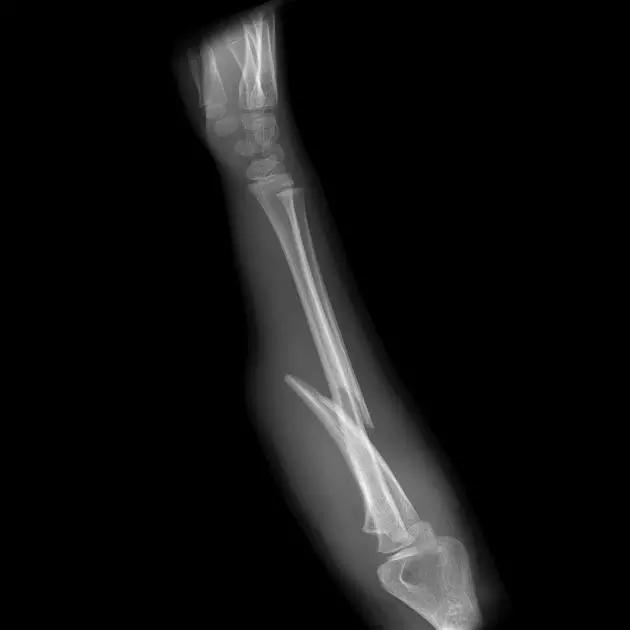

10. Galeazzi 骨折(盖氏骨折)

桡骨干下 1/3 骨折合并尺骨小头脱位。

盖氏骨折正侧位(来源:Orthobullets)